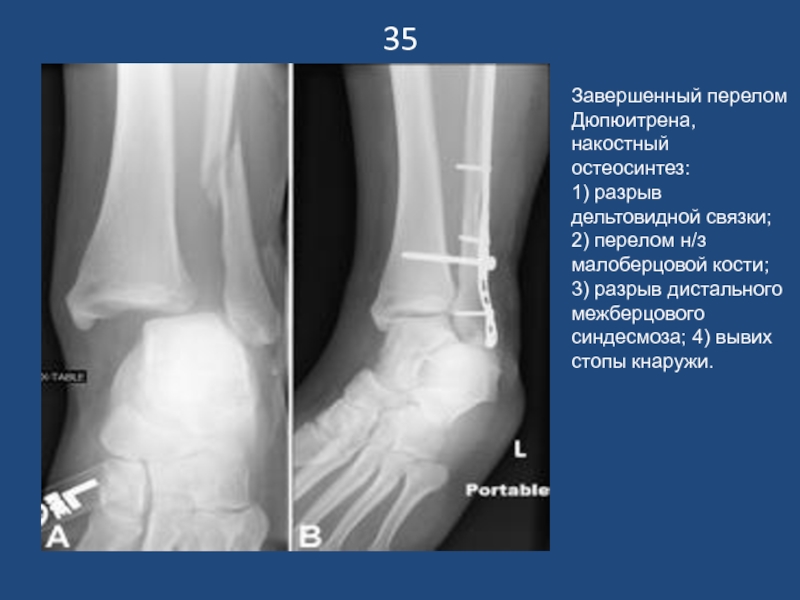

Слайд 3635

Завершенный перелом Дюпюитрена, накостный остеосинтез:

1) разрыв дельтовидной связки; 2) перелом

н/з малоберцовой кости;

3) разрыв дистального межберцового синдесмоза; 4) вывих стопы

кнаружи.

35Завершенный перелом Дюпюитрена, накостный остеосинтез:1) разрыв дельтовидной связки; 2) перелом н/з малоберцовой кости;3) разрыв дистального межберцового синдесмоза;